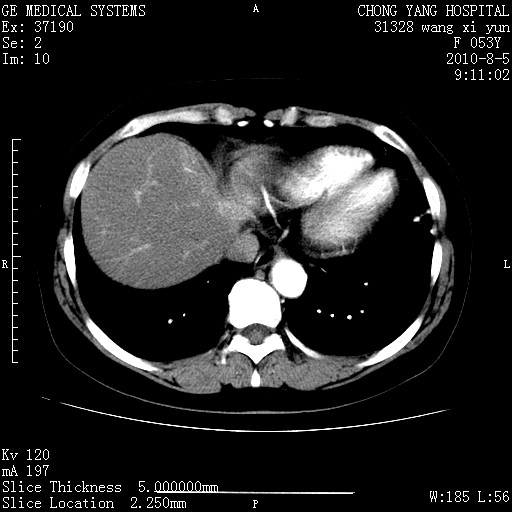

标题: CT28214:F41Y 血尿二十天,建议盆腔平扫加增强。

胆管细胞ca?

1)考虑肝左叶胆管细胞癌。2)脂肪肝。

支持胆管细胞ca。